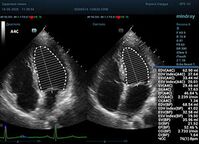

С появлением В режима реализовалась возможность визуализации всех сегментов миокарда из парастернальных и апикальных сечений. Метод Teicholtz в широкой практике сменился методом дисков. Метод дисков, или метод Simpson, позволяет разбить левый желудочек на 20 дисков, с расчетом объема каждого из них. Используя 2 перпендикулярных сечения, апикальные двух и четырех камерное, мы приближаемся к значению реального объема левого желудочка. Исследователь обводит интерфейс эндокард – кровь в фазу диастолы и фазу систолы. Линия простирается от кольца митрального клапана и до кольца митрального клапана, четко разграничивая объем желудочка от предсердия. Для достоверного изменения необходимо использовать ЭКГ канал.

Что могут предложить современные приборы? Приборы нашего времени являются мощными вычислительными машинами, способными обрабатывать полученную информацию даже без помощи человека. Система автоматического вычисления фракции выброса – AUTO EF на приборах серии Resona компании Mindray сделает все за вас. За пару секунд прибор сам отыщет нужную фазу сердечного цикла и произведёт измерение и расчеты, а также покажет график изменения объема в сердечном цикле. От Вас требуется только получить качественное 4С и 2С сечение. Впрочем, прибор всегда оставляет возможность коррекции, если доктор имеет свое мнение на расположение точек планиметрии или момента измерения по ЭКГ каналу.